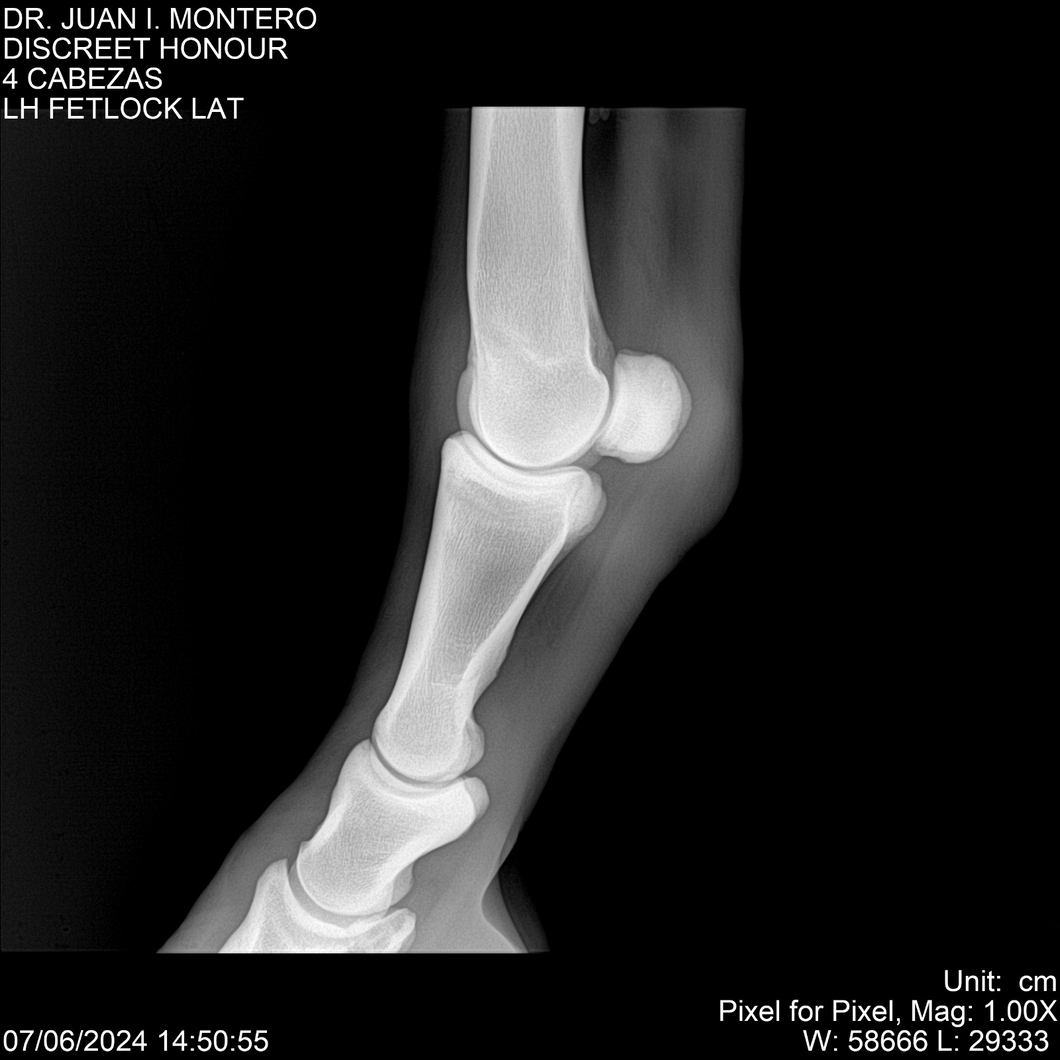

LOTE 6, DISCREET HONOUR 🔥 🔥 🔥 Lote Anterior Volver al remate Lote Siguiente Ficha Contacto Montevideo - Ficha del Lote Identificador: #281093 Categoría: Yeguarizos Montevideo - 82 Visualizaciones ClicData Contacto Empresa: Abelenda N. R., Walter Hugo Nombre*: Teléfono* : E-mail* : Mensaje Enviar Registrese gratis Este contenido Exclusivo está disponible sólo para usuarios registrados Ingresar